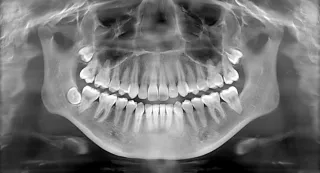

A panoramic X-ray takes one wide picture of your whole mouth. For wisdom teeth, it shows the exact position and orientation of the teeth, which can’t be seen in a regular photo. This helps the dentist plan for a safe extraction. If you’re using insurance, the panoramic X-ray also helps determine which type of extraction is needed so the right codes can be sent. The process is quick, easy, and painless.